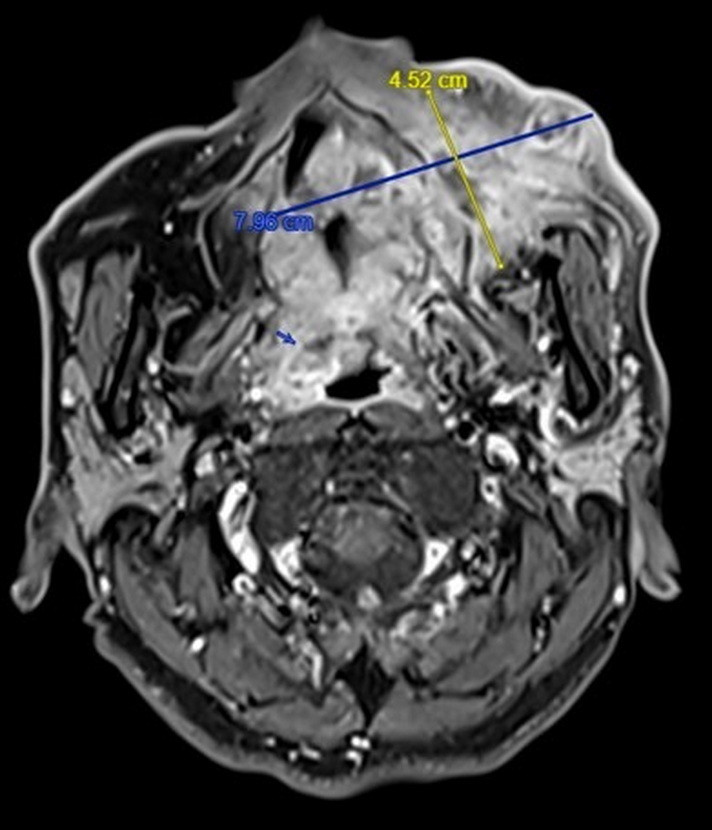

收治這名病患的彰基總院長陳穆寬表示,這名病患手術前的核磁共振顯示已是口腔癌末期(4期),腫瘤已經侵犯口腔、鼻竇及顏面皮膚,範圍已經達8公分,腫瘤範圍大,手術需要進行根治切除(包括半個口腔、鼻竇、及顏面)、頸部淋巴廓清術還有移植重建,手術治療過程耗時,對外觀影響也大。